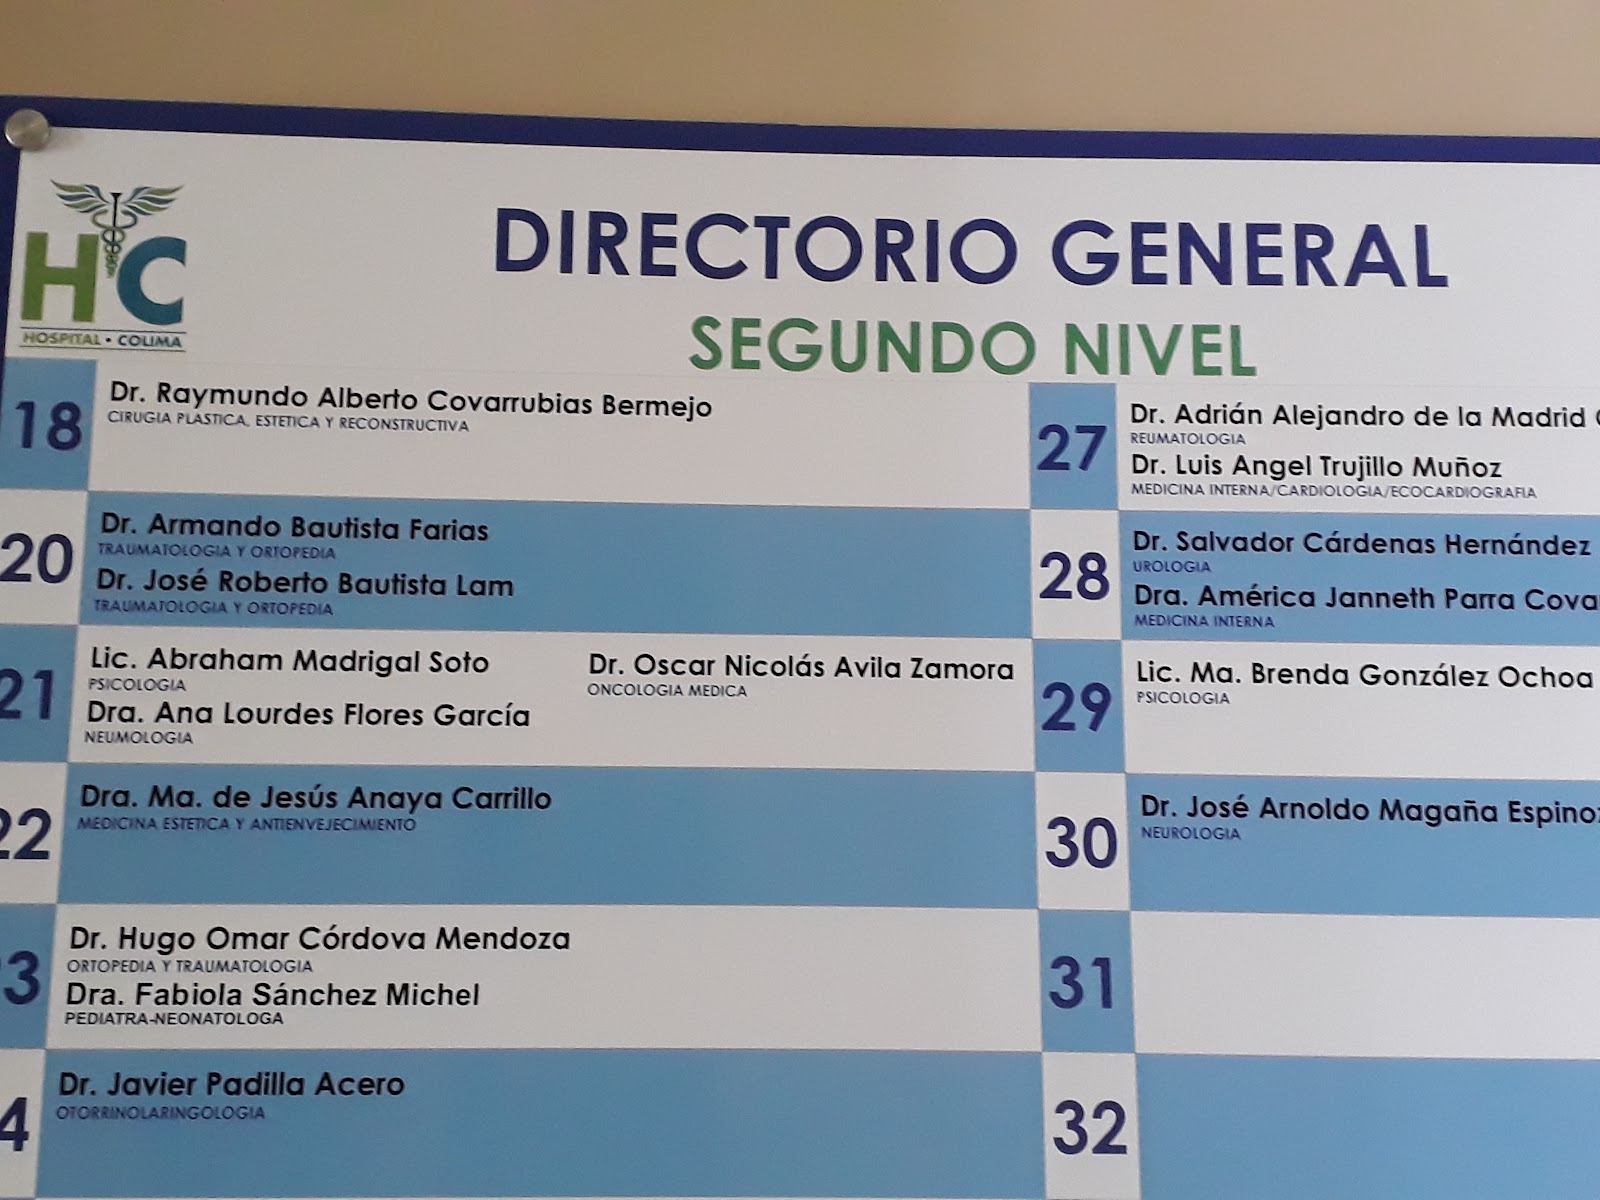

El Dr. Ulises Mejía es un urólogo destacado en Colima, reconocido por su profesionalismo y atención personalizada. Ubicado en Av. Constitución 2080, Puerta del Sol, ofrece servicios especializados en salud urológica para pacientes que buscan un cuidado integral y de calidad. Con una calificación de 5 estrellas basada en 10 opiniones, sus pacientes destacan su capacidad, inteligencia y dedicación en cada consulta y procedimiento. El Dr. Mejía se caracteriza por brindar un trato cercano y atento, asegurando que cada paciente reciba un diagnóstico preciso y un tratamiento efectivo. Sus servicios incluyen diagnóstico y manejo de enfermedades urológicas, cirugías y seguimiento postoperatorio, siempre con un enfoque humanizado. Para agendar una cita o solicitar información, puede contactarse al teléfono 312 114 8230 o visitar su perfil profesional en Instagram. Si busca un especialista confiable y con amplia experiencia en Colima, el Dr. Ulises Mejía es una opción recomendada para el cuidado de su salud urológica.

Dr. Ulises Mejía is a highly regarded urologist based in Colima, known for his professionalism and personalized care. Located at Av. Constitución 2080, Puerta del Sol, he provides specialized urological health services to patients seeking comprehensive and quality care. With a perfect 5-star rating from 10 reviews, patients highlight his expertise, intelligence, and dedication during every consultation and procedure. Dr. Mejía is recognized for his attentive and compassionate approach, ensuring accurate diagnoses and effective treatments. His services include diagnosis and management of urological conditions, surgeries, and postoperative follow-up, all delivered with a patient-centered focus. To schedule an appointment or request more information, contact him at 312 114 8230 or visit his professional Instagram profile. For those looking for a reliable and experienced urologist in Colima, Dr. Ulises Mejía is a highly recommended choice for urological health care.